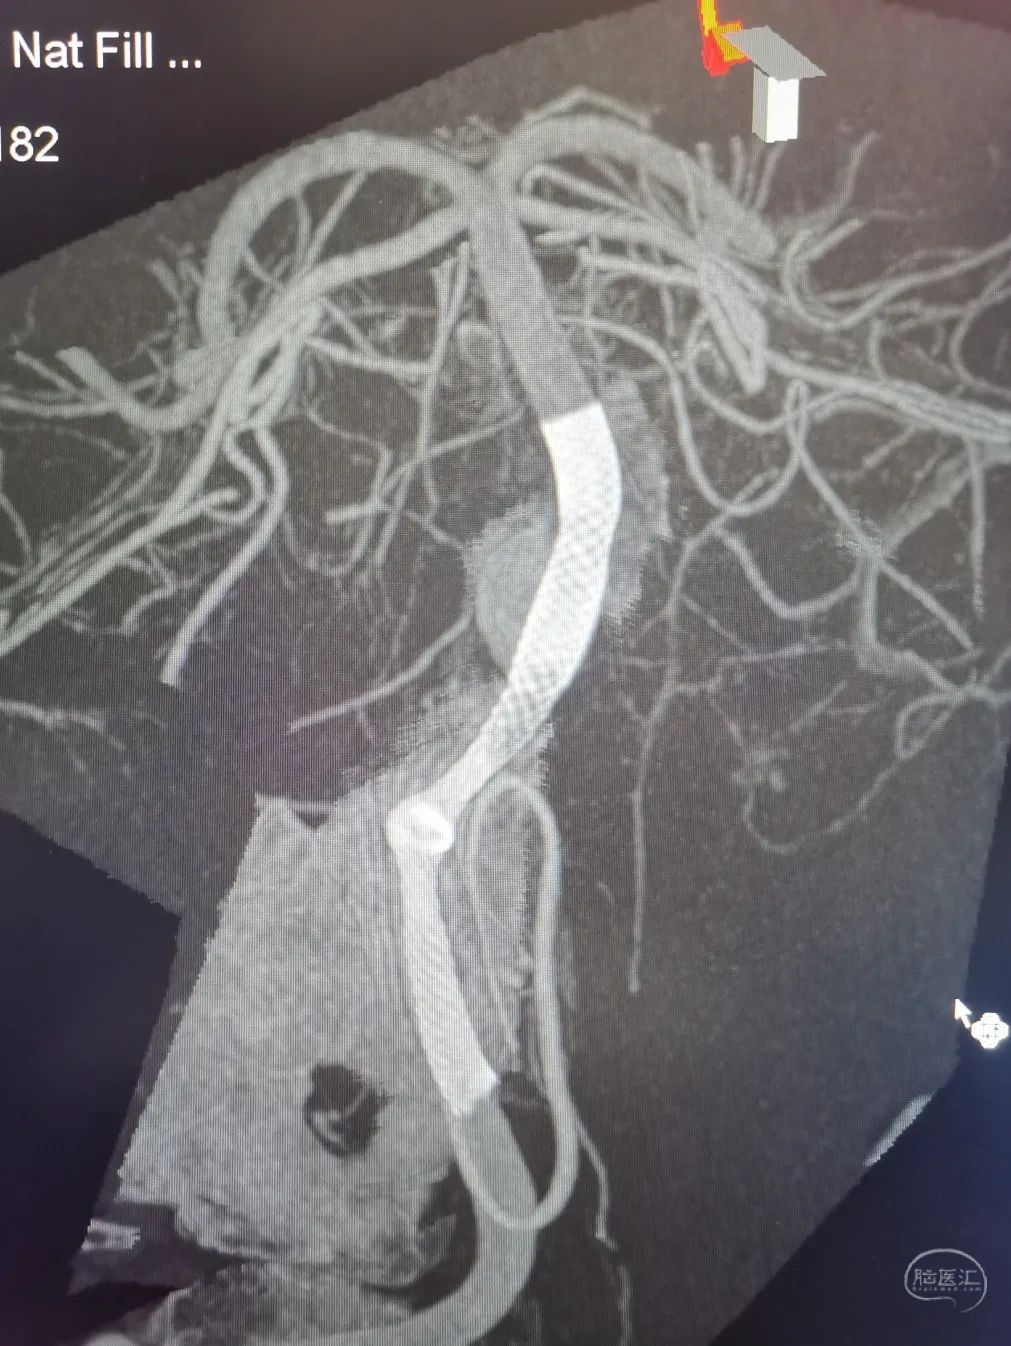

3D重建显示基底动脉下部、双椎结合部、左椎多发夹层动脉瘤:

双抗5天后行左侧椎动脉多发夹层动脉瘤Pipeline™ Flex 血流导向密网支架植入术。

Pipeline™ Flex 血流导向密网支架 PED-325-35

将Phenom™ 27微导管超选进入左侧大脑后动脉内,释放一枚3.25×35mm Pipeline™ Flex血流导向密网支架,远端定位在动脉瘤以远7mm,在动脉瘤处推密,近端定位在PICA起始部上端或远端,支架打开顺利。导引导管内推注替罗非班12mL,支架导管及微导管常规按摩,促进支架贴壁。

术后造影显示动脉瘤内造影剂滞留明显,载瘤动脉通畅。

支架CT: